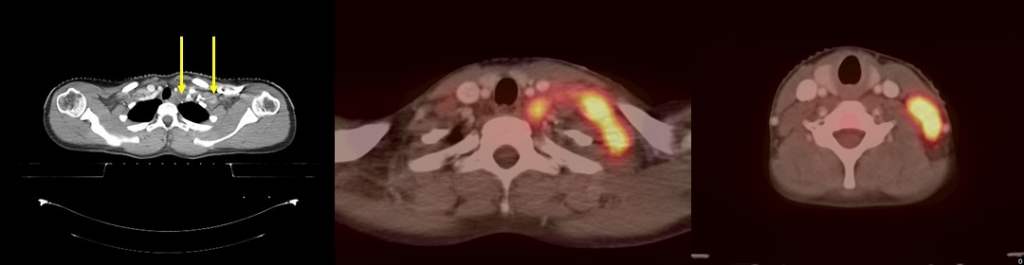

Scanner cervico thoraco-abdomino-pelvien : Atteinte ganglionnaire cervicale gauche, médiastin latéro-trachéale gauche. Absence d’anomalie sous-diaphragmatique |

TEP-FDG : adénopathies hypermétaboliques jugulo-carotidienne, cervicale basse gauche, latéro-trachéale. |